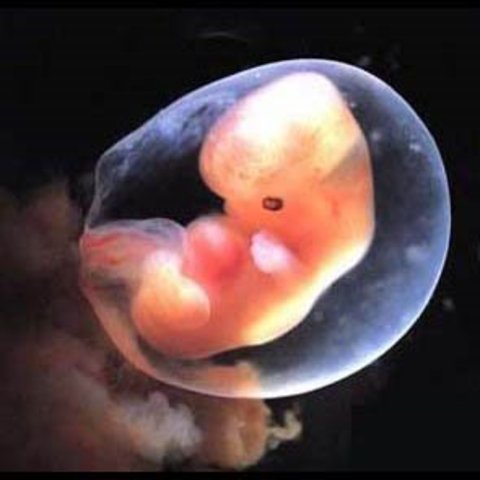

Month Two

Size at the end of this month should be around 1 and 1/8 of an inch. In boys, gender also starts to become visually distinguishable.

• Arm and Leg Buds Form

Arm and Leg Buds Form

• Back Begins to Straighten Out from the C-Shape

Back Begins to Straighten Out from the C-Shape